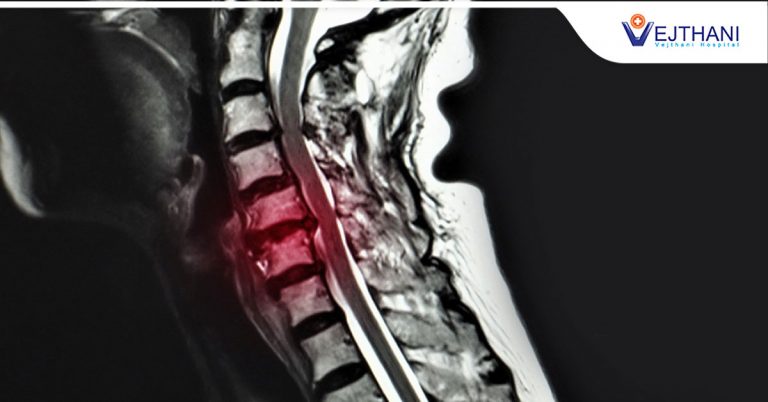

อย่างไรก็ตาม หากพบว่ามีอาการปวดหลังเรื้อรัง ปวดหลังร้าวลง ควรรีบเข้ามาพบแพทย์เฉพาะทาง เพื่อเข้ารับการตรวจวินิจฉัยและแนะนำวิธีการรักษาได้อย่างถูกต้อง

ศูนย์กระดูกสันหลัง โรงพยาบาลเวชธานี